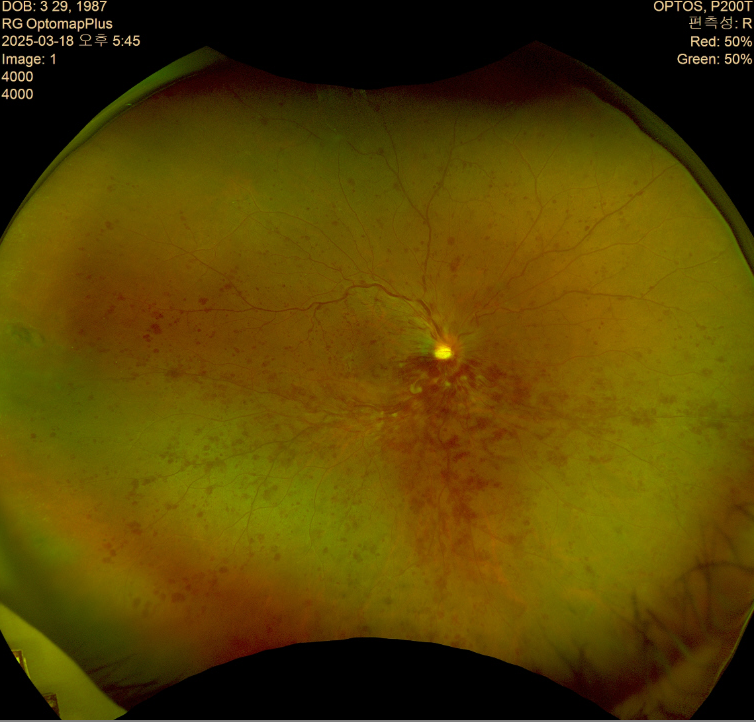

오른쪽 눈 광각안저사진

1. 첫 번째 이미지 (망막 촬영, Optos) 분석

- 망막 중심부(황반)와 시신경유두(optic disc)가 보이며, 망막 곳곳에 붉은색 병변이 관찰됨.

- 일반적으로 이런 소견은 당뇨망막병증(Diabetic Retinopathy), 황반변성(Age-related Macular Degeneration, AMD), 또는 망막출혈(Retinal Hemorrhage) 등의 가능성을 시사함.

- 주변부로 갈수록 망막이 흐릿해지며, 경미한 부종이나 혈관 이상이 있을 가능성이 있음.